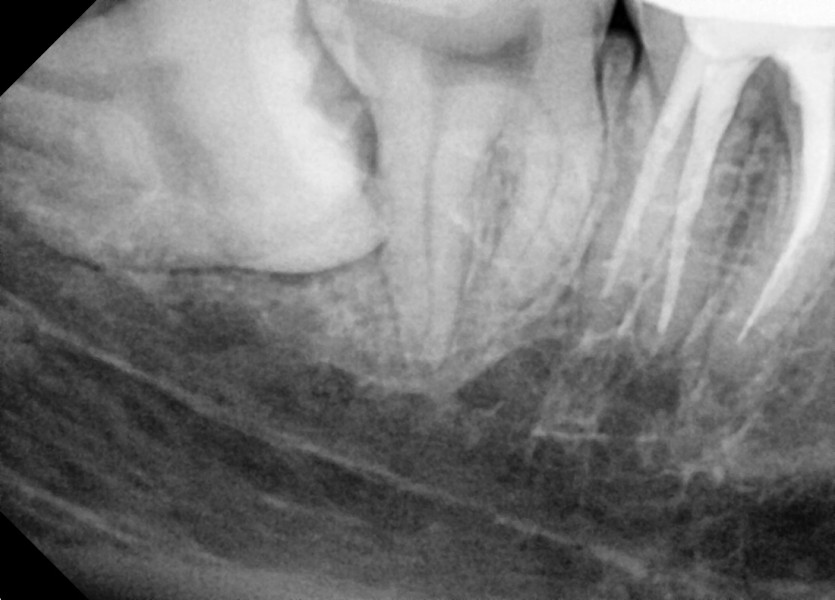

#48 사랑니 발치

구강 외과 전문의가 당일 발치했습니다.